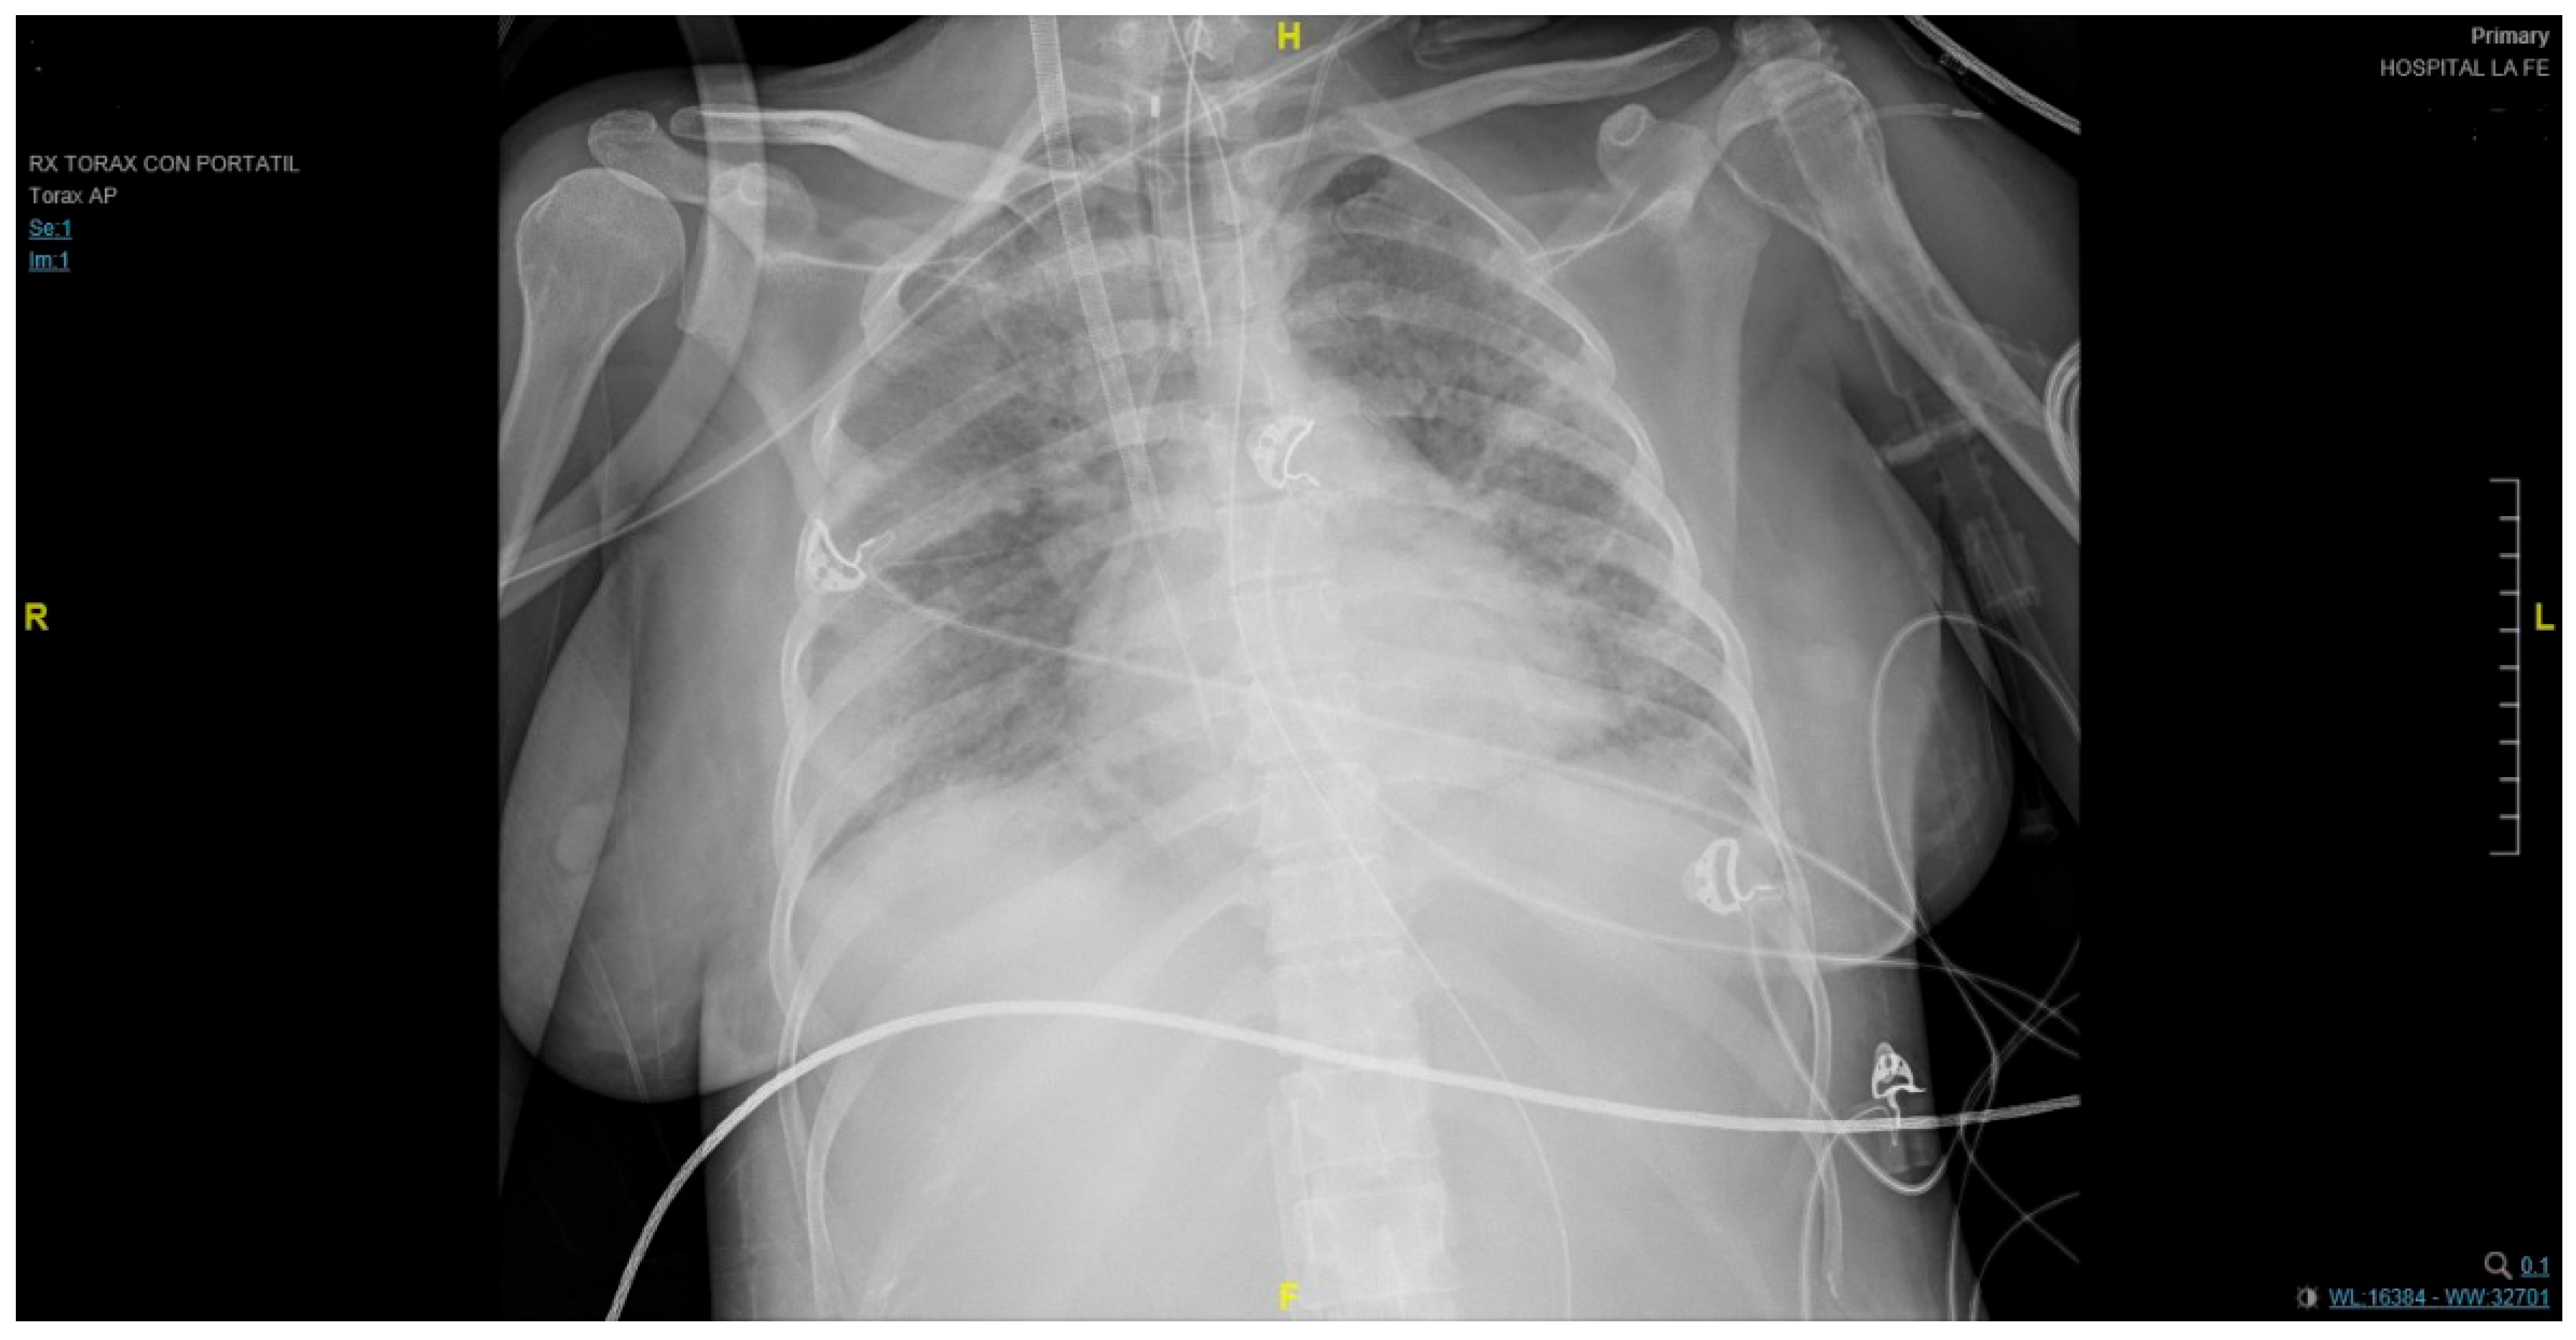

At the emergency department, the patient manifested pleuritic chest pain, anosmia, dysgeusia, tachypnea, and dyspnea with minimal effort. Arterial blood gas displayed respiratory alkalosis, hypoxemia, and an inspired oxygen fraction index (PAFI) of 143. Blood tests showed a reactive C-protein (CRP) of 162.2 and a D-dimer of 55.800. No other parameters were abnormal. A chest X-ray revealed extensive bilateral areas of consolidation. Thus, she was admitted to the hospital. Low-molecular-weight heparin (LMWH) of 40 mg/12 h and dexamethasone were initially administered.

The patient required admission into the ICU one day after being admitted into the hospital due to respiratory failure requiring high-flow nasal oxygen therapy at the beginning. Later, intermittent noninvasive mechanical ventilation (BiPAP) was administered because of her poor clinical evolution. Nonetheless, on the fourth day in the ICU, the patient required orotracheal intubation for mechanical ventilation with a neuromuscular blockade. Functional deterioration persisted despite prone positioning (adapted to the pregnant woman’s condition) and nitric oxide therapy. Hypoxemic respiratory failure (p02 58 mmHg) was diagnosed. Thus, circulatory assistance using ECMO with venovenous access (right femoral–right jugular) under prophylactic antibiotic therapy was performed (Figure 1). During the entire hospital admission, a close pregnancy follow-up was carried out through maternal and fetal assessments that included a fetal ultrasound every 24–72 h.

Figure 1. An anteroposterior chest X-ray revealed extensive bilateral areas of consolidation and the endotracheal tube at 2 cm of carina.